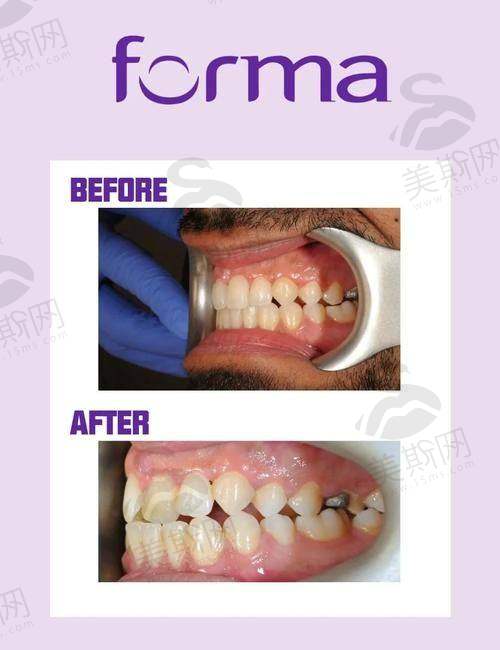

牙齿矫正中 心:提供传统金属托槽、陶瓷自锁托槽、隐形矫正(隐适美、时代天使)、儿童早期干预矫正等,配备iTero口内扫描仪,3分钟即可预览矫正成效。

美学修复科:开展全瓷冠、牙齿贴面、嵌体修复等,运用数字化微笑设计技术,结合患者面部比例定制修复方案,兼顾功能与美观。